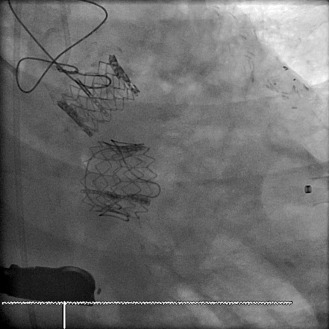

Transcatheter/percutaneously inserted heart valves are increasingly implanted. Most commonly, they are inserted into the pulmonic position or right heart conduits in the previously repaired congenital heart disease population ( Figs. 13-1 and 13-2 ) and into the aortic position ( Table 13-1 ; Graphics 13-1 and 13-2 ; Figs. 13-3 to 13-10 ), but they can also be placed into atrioventricular valve positions and into bioprostheses or conduits in any position.

Percutaneous/transcatheter heart valves are constructed of either bovine jugular venous valves that are suspended on wire mesh cages (Bonhoeffer design/Melody Transcatheter Pulmonary Valve–TPV, Medtronic), or consist of a valve created from bovine pericardial tissue that is suspended on wire mesh cages (Edwards Sapien and Medtronic CoreValve). Percutaneous aortic valve implantation is currently one of the most rapidly proliferating percutaneous interventions in the world ( Figs. 13-11 to 13-13 ).